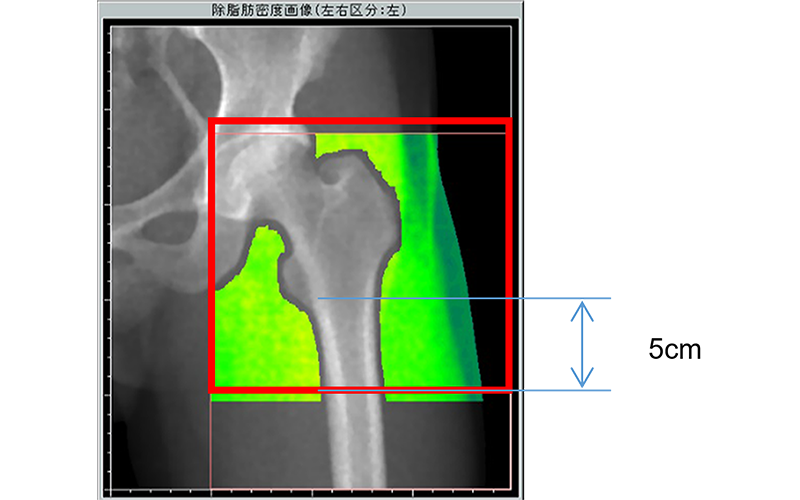

骨密度装置での体組成範囲は、大腿近位部(小転子下5㎝まで)(図2)とし、測定側大腿骨頚部にインプラントがある、下肢動脈に石灰化がある、測定体位をとれない、医師または測定技師が測定不可と判断した者は除く。

体組成解析範囲;図1参照

図2 DXA測定範囲